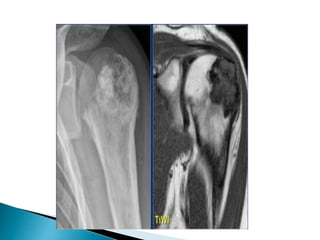

 Here alesion located in the epi- and metaphysis of the proximal humerus.  The lesion is predominantly calcified.  Coronal T1W image shows lobulated margins due to the calcifications.

 A juxtacortical chondrosarcomahas be considered in the differential diagnosis when a mineralized lesion adjacent to the cortical bone is seen.

Here a partially calcifiedmass against the proximal humerus with involvement of the cortical bone on an axial CT image

 .  T2-weightedMR image reveals a lobulated mass with high signal intensity. The bone marrow compartment is not involved which is important for the surgical strategy. A periosteal chondroma may have the same imaging characteristics, however, these are almost always much smaller